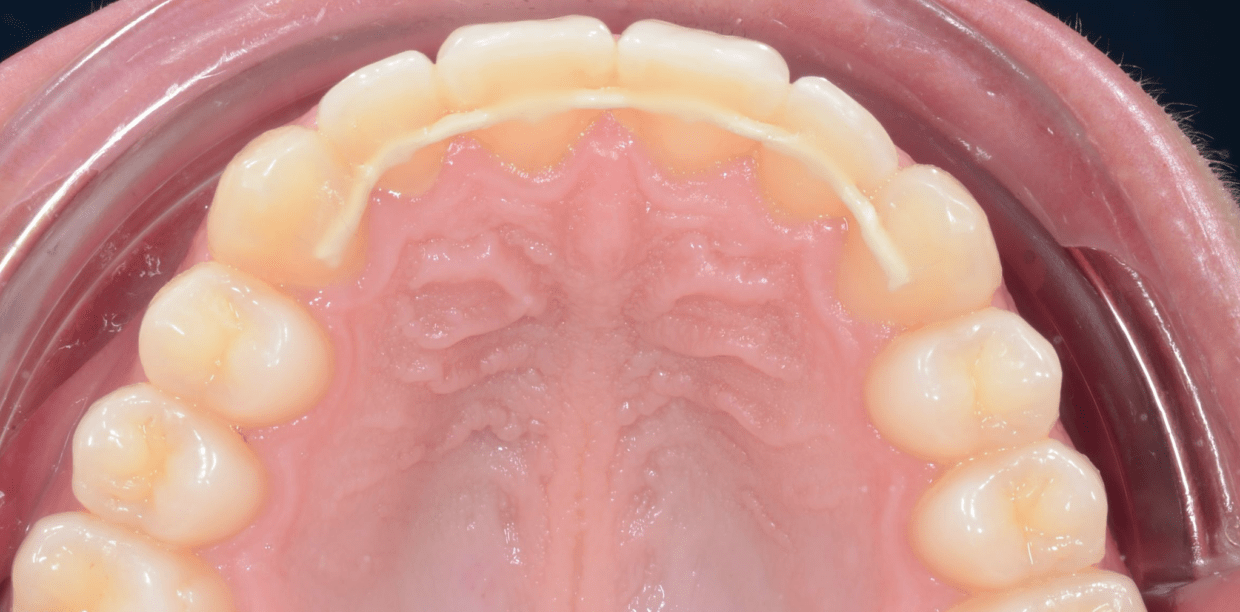

Cas cliniques

Simple - A2

Simple - A2

Simple - A2

Simple - A2

Simple - A2

Simple - A2

Simple - A2

Simple - A2